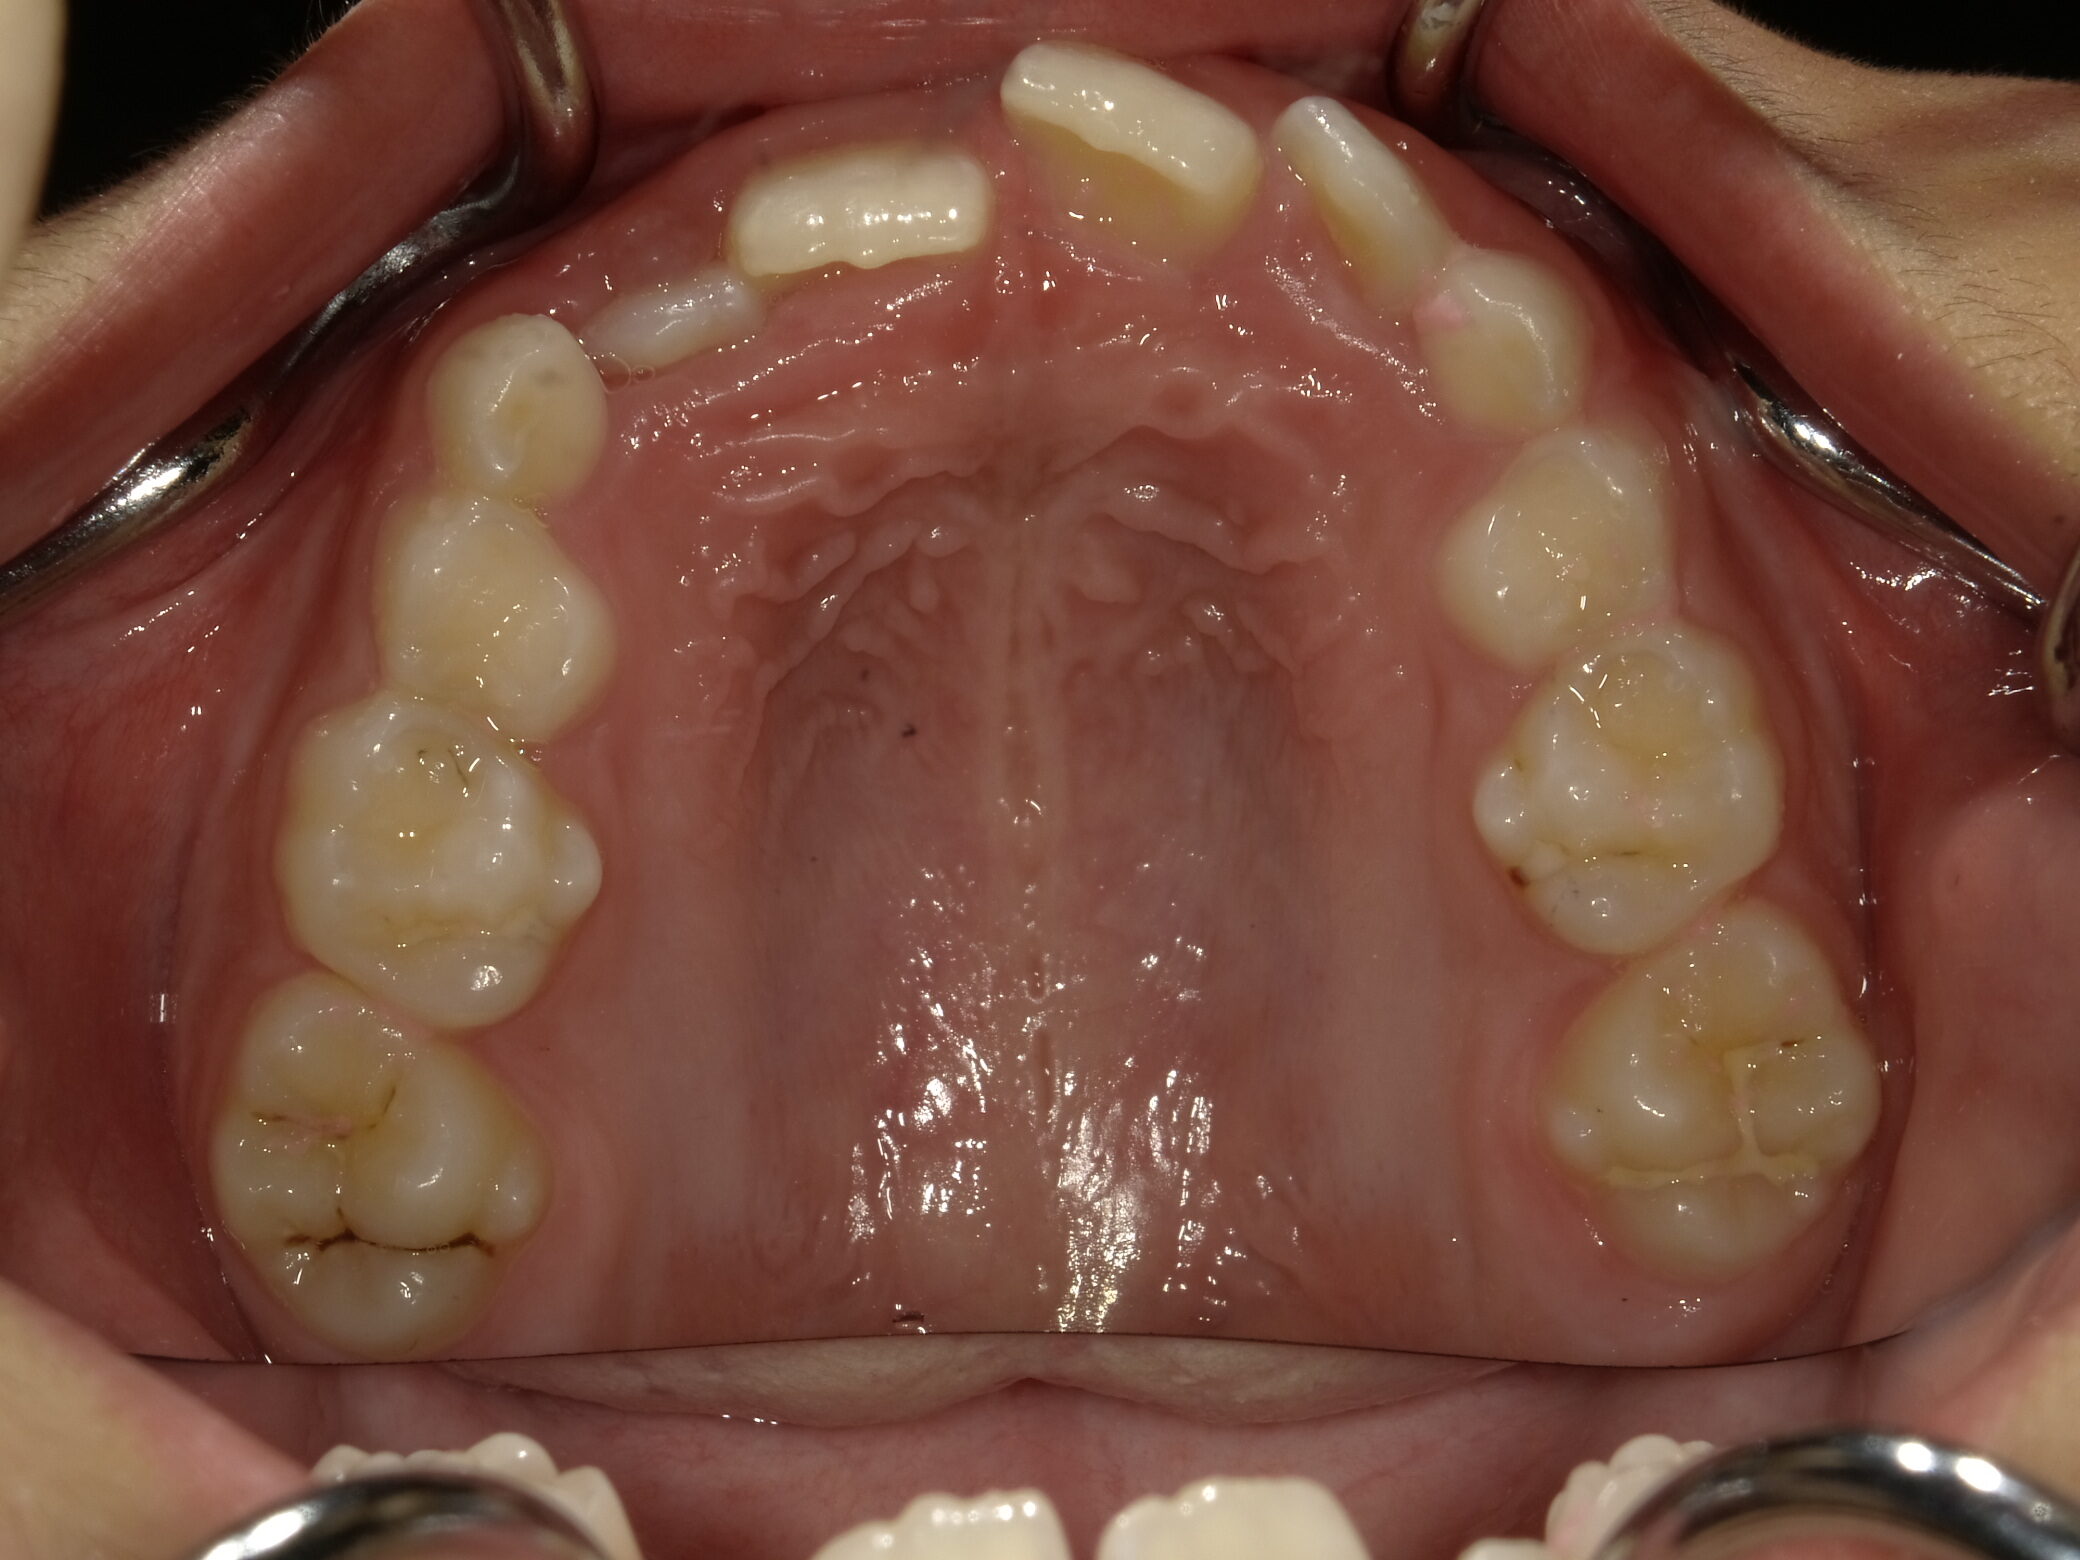

| 症例分類 | 交叉咬合 |

|---|---|

| 主訴 | 前歯がずれて咬んでいる |

| 年齢 | 9歳5ヶ月 |

| 性別 | 女性 |

| 抜歯部位 | なし |

| 使用装置 | 拡大装置、上顎前歯部のセクショナルアーチ装置、取り外し式保定装置 |

| 治療期間 | 1年2ヶ月 |

| 費用 | 相談料0円、検査料50,000円 動的矯正治療費330,000円 調整料6600円×15回分 保定装置料0円 |

| リスク・注意点 | 個々の歯の大きさに対して顎が小さく、歯が並ぶスペースが不足したために交叉咬合が生じています。これらを改善するために、幅の狭搾している歯列を側方に拡大した後、前歯を排列しました。

歯の動き方には個人差があり、予想された治療期間が延長する可能性があります。 治療中は矯正歯科装置が歯の表面に付いており、歯が磨きにくくなるため、むし歯や歯周病が生じるリスクが高まります。ハミガキを適切に行ってお口の中を常に清潔に保ち、さらに、かかりつけ歯科医に定期的に受診することが大切です。 矯正歯科装置の使用状況、定期的な通院など、矯正歯科治療には患者さんの協力が必要であり、それらが治療結果や治療期間に影響します。 治療の経過によっては当初予定していた治療計画を変更する可能性があります。 保定装置の装着時間が十分確保できない場合、歯並びや、咬み合せの「後戻り」が生じる可能性があります。 上下両側第二大臼歯の萌出を観察する必要があります。 |